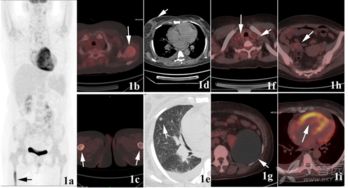

惡性腫瘤細胞由于代謝旺盛而對葡萄糖的需求增加,因此18FDG后,大多數(shù)腫瘤病灶會表現(xiàn)為對18FDG的高攝取,因此可應用18FDG

PET-CT顯像可早期發(fā)現(xiàn)全身腫瘤原發(fā)及轉移病灶,準確判斷其良、惡性,從而正確指導臨床治療決策。但是18F-FDG有著放射性核半衰期,這就總讓受檢者們擔心,做完PET